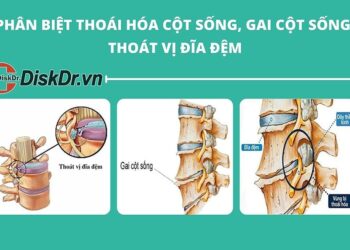

- Thoái hóa khớp: Đây là bệnh lý thường gặp ở tuổi trung niên, là nguyên nhân gây đau nhức xương khớp thường gặp nhất.